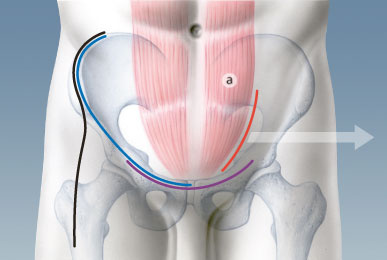

Abb. 4

Zwei Jahre nach der Versorgung über den «Pararectus»-Zugang zeigt das Röntgenbild des Beckens eine vollständige Heilung der anatomisch gerichteten Acetabulumfraktur ohne Zeichen einer Hüftgelenksarthrose. Der Patient ist beschwerdefrei.

Bei den ersten 20 Patienten mit einem Altersdurchschnitt von 59Jahren – der älteste war 90-jährig – zeigten sich während und nach der Operation keine wesentlichen Komplikationen (Abb. 3). Die Operation dauerte durchschnittlich drei Stunden. In der postoperativen Computertomographie wurde bei 19 Patienten eine anatomische Reposition mit weniger als 1 mm Verschiebung und nur bei einem Patienten eine solche von 2 mm festgestellt. Nach zwei Jahren konnten 17 Patienten nachuntersucht werden. Zwei Patienten erhielten 4 respektive 18 Monate nach der Operation eine Hüfttotalprothese, alle anderen Patienten (88%) hatten eine exzellente oder gute Funktion (Abb. 4). Der «Pararectus»-Zugang ist nicht nur ein minimalinvasiver Zugang, sondern scheint die Versorgung von Acetabulumfrakturen auch bei älteren Patienten zu verbessern. Er sollte jedoch nur von einem erfahrenen Beckenspezialisten angewandt werden, damit bei dieser anspruchsvollen und hochspezialisierten Chirurgie Komplikationen vermieden und gute Ergebnisse erreicht werden.